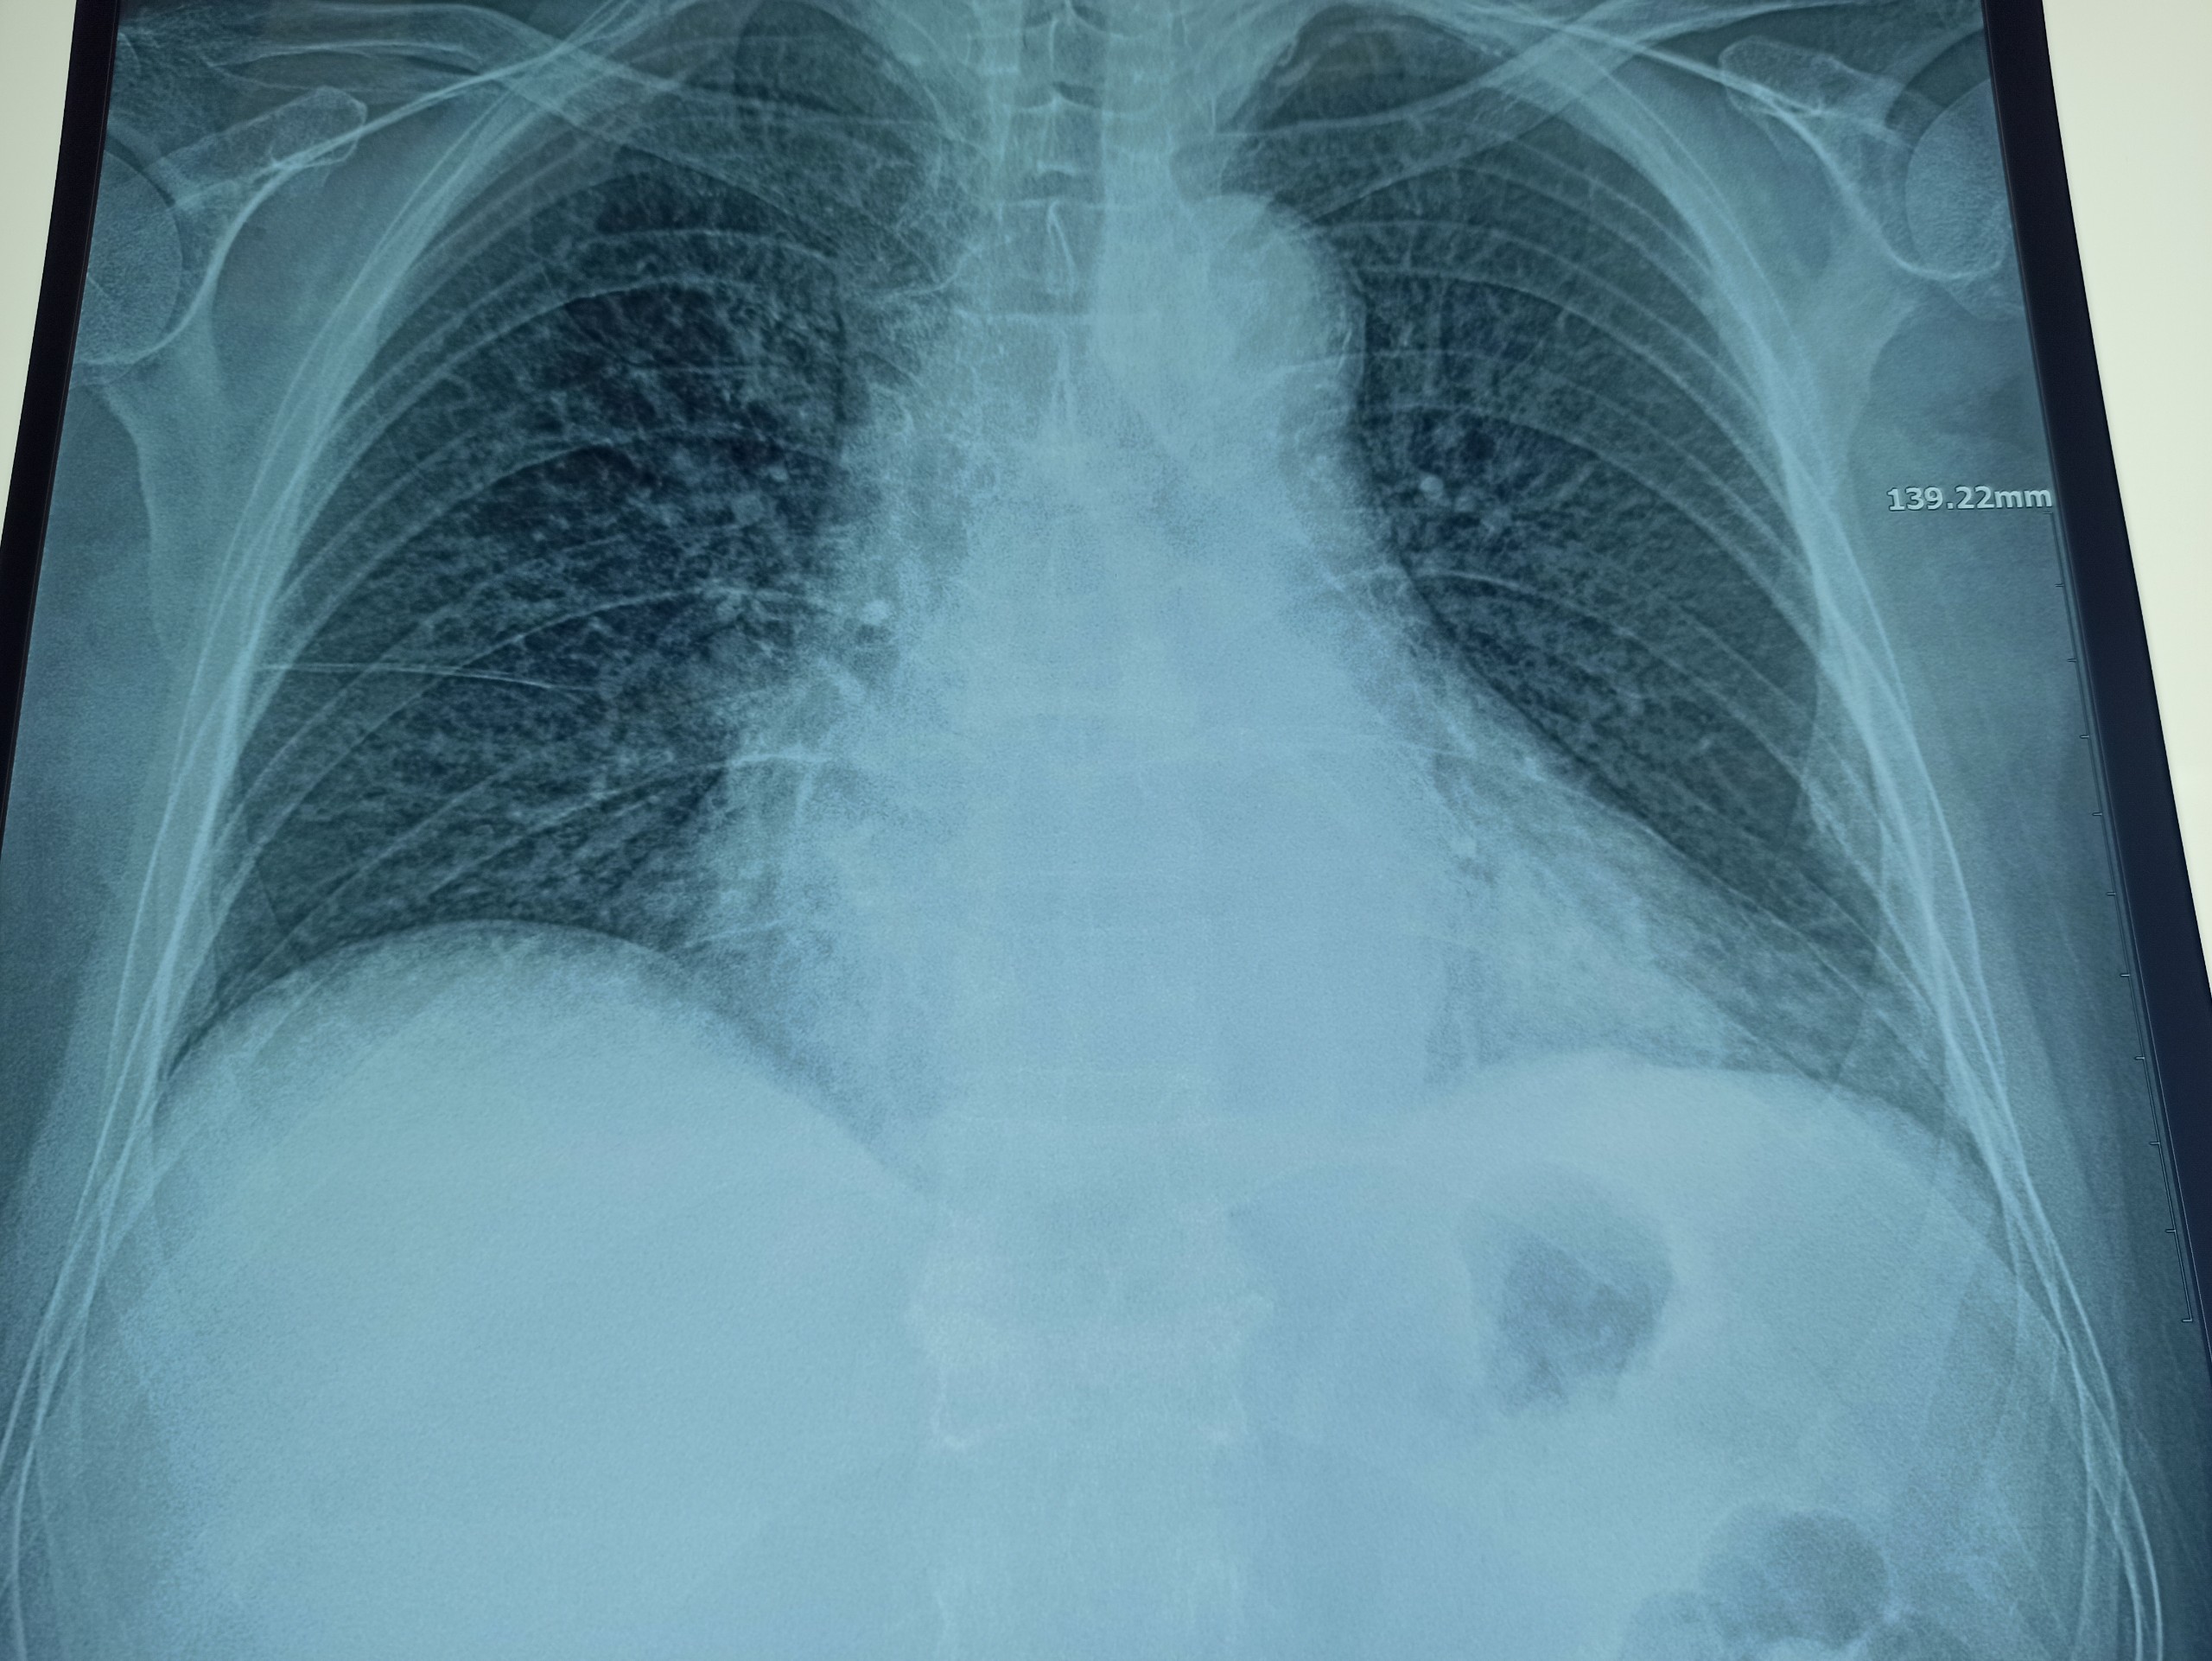

Hình ảnh bóng tim to trên phim X-quang